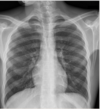

A 72 year old man with background history of multiple myeloma presents to the emergency department with shortness of breath, sore throat runny node and a cough. He had chemotherapy 4 days previously. Observations: HR 118 bpm, BP 90/60 mmHg, temperature 38.2°C, respiratory rate 25 /min, O2 saturation 75% on air.. Blood results: Hb 96 g/L WBC 0.9 x109/L CRP 115 mg/L U&E: normal Urinalysis: 1+ blood and 1+ protein, nitrite -ve Chest X-ray shown in image. What is the most likely diagnosis? 1 - Aspiration pneumonia 2 - Neutropenic sepsis 3 - Lobar pneumonia 4 - Urinary tract infection 5 - Upper respiratory tract infection

2 - Neutropenic sepsis